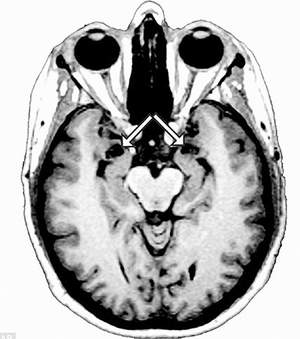

Các nhà nghiên cứu thần kinh học tại trường Đại học Iowa ở thành phố Iowa, bang Iowa (Mỹ) đang trong thời gian nghiên cứu về trường hợp của S.M trong suốt một thời gian dài bởi vì trường hợp của bà là đặc biệt hiếm gặp nó đã gây hư hại đến vùng hạch Amygdala ở cả hai bên bán cầu não của bà. Amygdala là một cấu trúc hình quả hạnh nhân đóng vai trò quan trọng trong việc hình thành nên sự sợ hãi và các trạng thái cảm xúc khác, mặc dù các chuyên gia nói rằng vai trò thực sự của cấu trúc này hiện vẫn chưa rõ ràng lắm. Sự hư hại của Amygdala ở người phụ nữ S.M được gây ra bởi một chứng bệnh Urbach-Wiethe (đây là một chứng bệnh hiếm gặp, nó là một chứng bệnh do rối loạn di truyền, gây thiếu hụt canxi và tổn thương đến hạch Amygdala). Theo ông Daniel Tranel, một trong những tác giả nghiên cứu kiêm giáo sư thần kinh học và tâm lý học tại trường Đại học Iowa, phát biểu: “Chúng tôi muốn biết rằng: Có hay không một dạng sợ hãi thông thường đã phản hồi đến S.M gây ra sự kích động sợ hãi ?”. Nhằm xác định những tác động đối với trường hợp hiếm gặp này trong việc phản hồi cảm giác sợ hãi, Daniel Tranel và các đồng nghiệp của mình đã cho S.M lần lượt tiếp xúc với những thứ mà người bình thường cảm thấy sợ hãi như nhện, rắn, một trong những ngôi nhà “ma” và xem những bộ phim kinh dị. Cùng với đó họ đã tiến hành thẩm định rất nhiều các câu hỏi về hội chứng sợ hãi của S.M trong giai đoạn thí nghiệm kéo dài 3 năm và cũng hỏi cảm giác của S.M để đánh giá các mức độ cảm xúc khác nhau tại những thời điểm ngẫu nhiên trong thời gian kéo dài 3 tháng.

S.M báo cáo rằng bà không có ấn tượng gì đối với những màn “tra tấn” của các nhà khoa học cũng như có báo cáo cho rằng bà S.M vẫn duy trì cảm xúc bình thường trong suốt thời gian diễn ra các cuộc thử nghiệm. Mặt khác, S.M cũng thể hiện các cảm xúc khác như vui mừng, hạnh phúc và buồn bã. Trong quá khứ, S.M từng va chạm với nhiều nỗi khổ đau. Bà từng bị doạ giết bằng súng, bằng dao và tưởng như sắp chết trong một vụ tai nạn. S.M nói với các nhà nghiên cứu rằng bà không có cảm giác sợ hãi trong suốt những thời kỳ diễn ra các đợt thử nghiệm. S.M cũng nhận thức rằng bà không có khả năng để phản ứng lại với nỗi sợ hãi trong khi người bình thường đã la hét thất thanh vì sợ. Theo TS. Jon Shaw, giáo sư tâm thần học tại trường Đại học Y khoa Miami (Mỹ): “Cơ thể của S.M đã không có các phản ứng cần thiết khi sợ hãi bởi vì hạch Amygdala không có trong não”. Daniel Tranel nói rằng cuộc nghiên cứu này cùng với những trải nghiệm trong quá khứ của S.M, đã chỉ ra rằng hạch Amygdala đóng một vai trò sống còn đối với con người trong việc phản hồi lại nỗi sợ hãi.